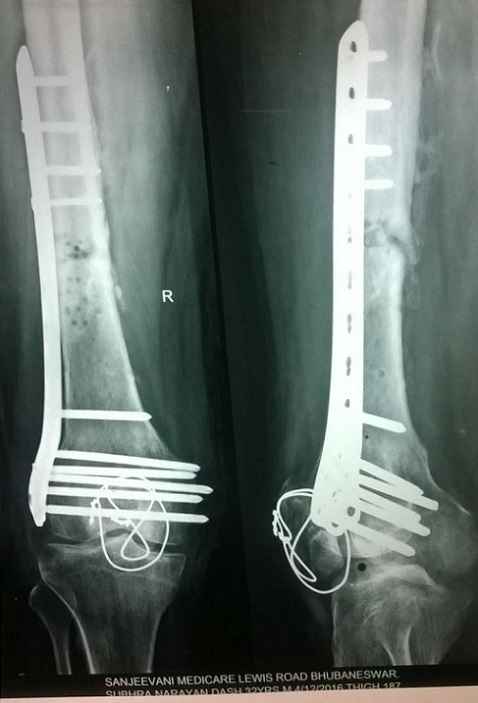

X-Ray of Subhra Narayan Das

Post operative treatment of this fracture was done with Laser. The patient is fine with out pain. Driving his car regularly without any complications.